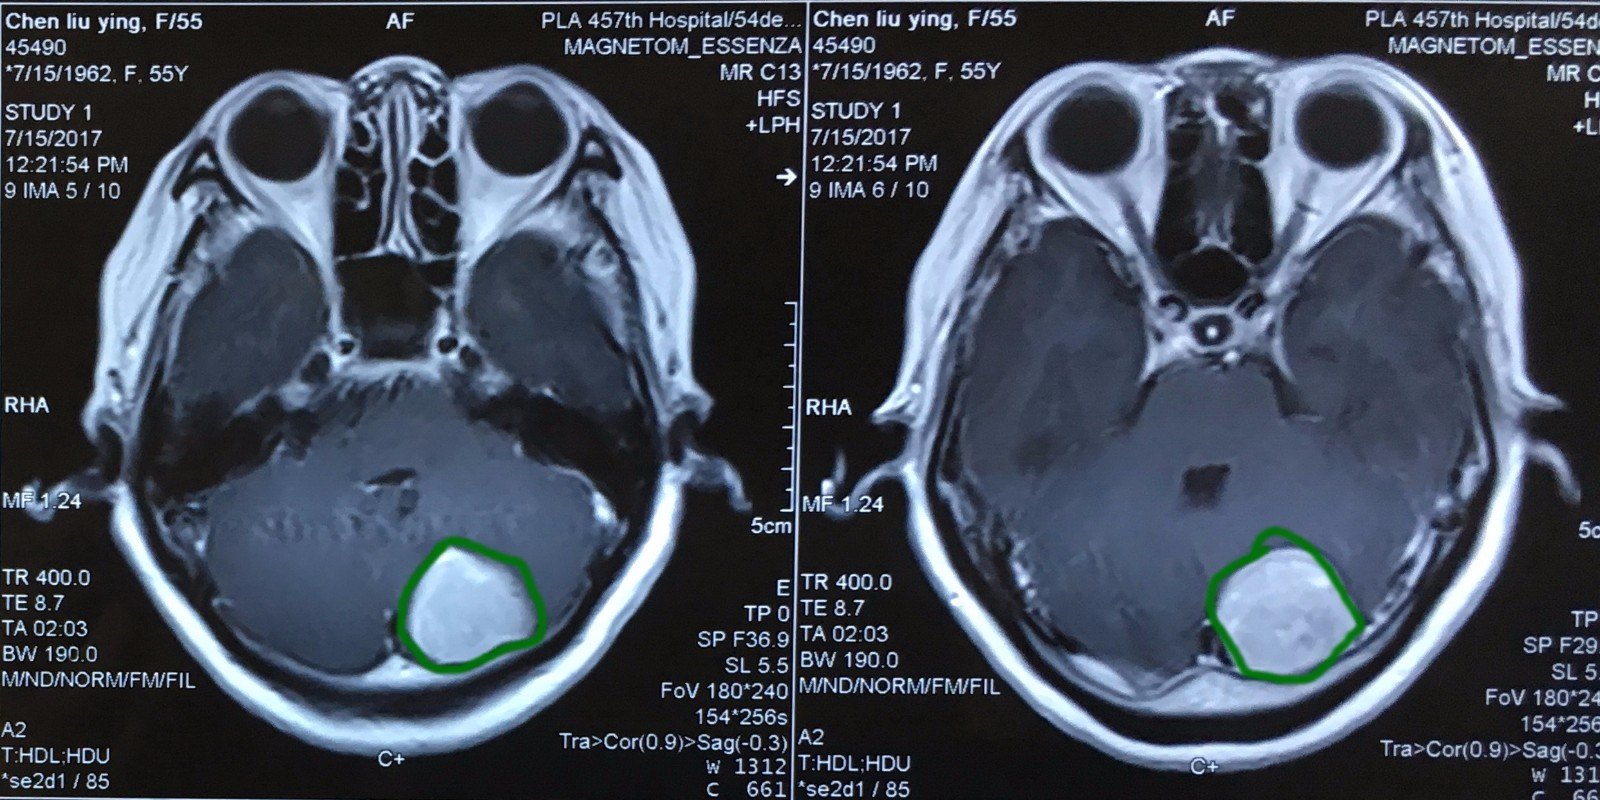

横窦天幕脑膜瘤手术一例 - 微医(挂号网)

图片尺寸1260x578